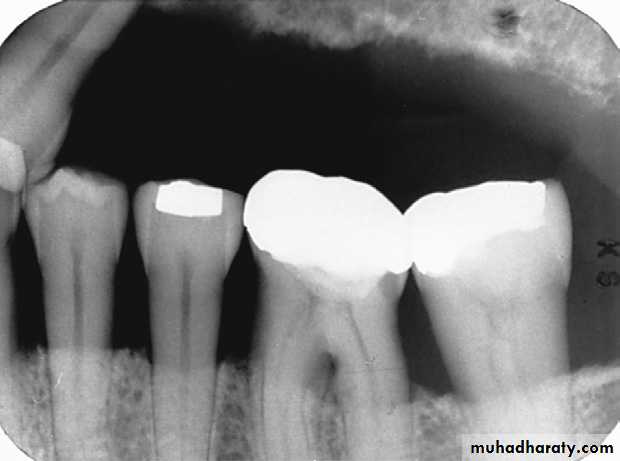

vertical (angular) bone loss:

Bone loss doesn’t occur in plane parallel to CEJs of adjacent teeth.Vertical bone loss

Vertical bone defects-are also called proximal intrabony defects. The defect extends apically2- Distribution